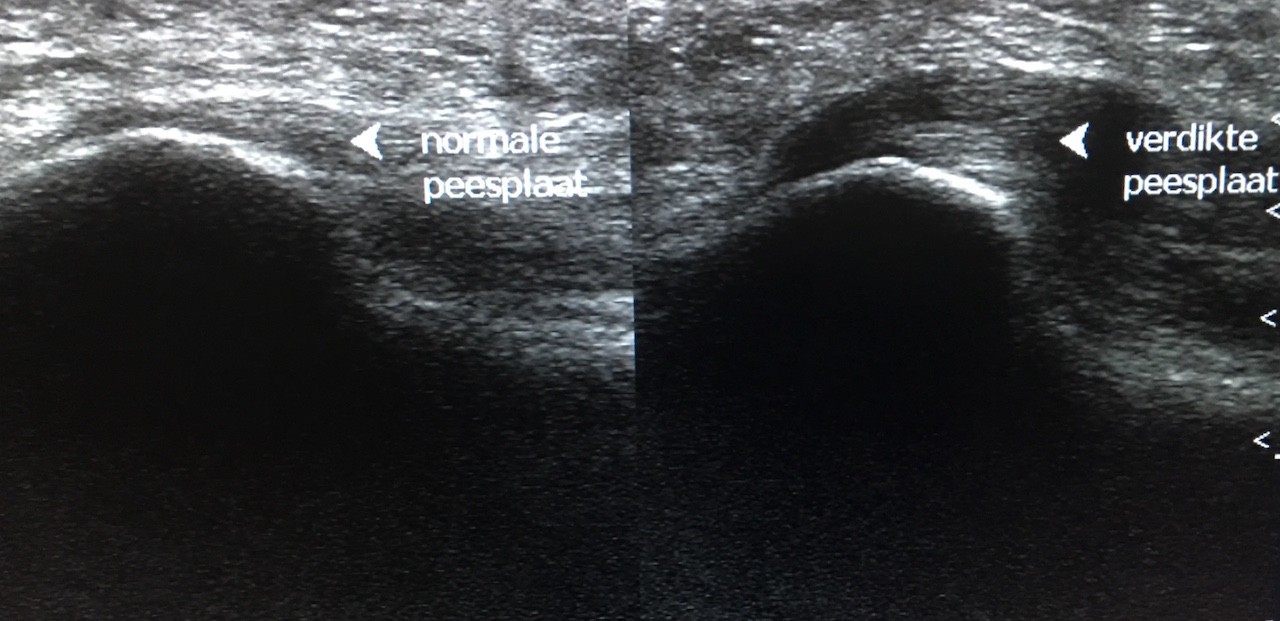

Sinds een jaar of tien geleden echografie zijn intrede deed binnen de fysiotherapie kon deze platte peesplaat zelf ook bekeken worden en al snel bleek dat het niet de hielspoor (het aangroeisel) maar de overbelaste en verdikte platte peesplaat was die de hielpijn veroorzaakte. Sommige zorgverleners zijn daar niet van op de hoogte en noemen de hielpijn nog altijd ‘hielspoor’, terwijl het in feite om een peesplaatontsteking (fasciitis plantaris) gaat.